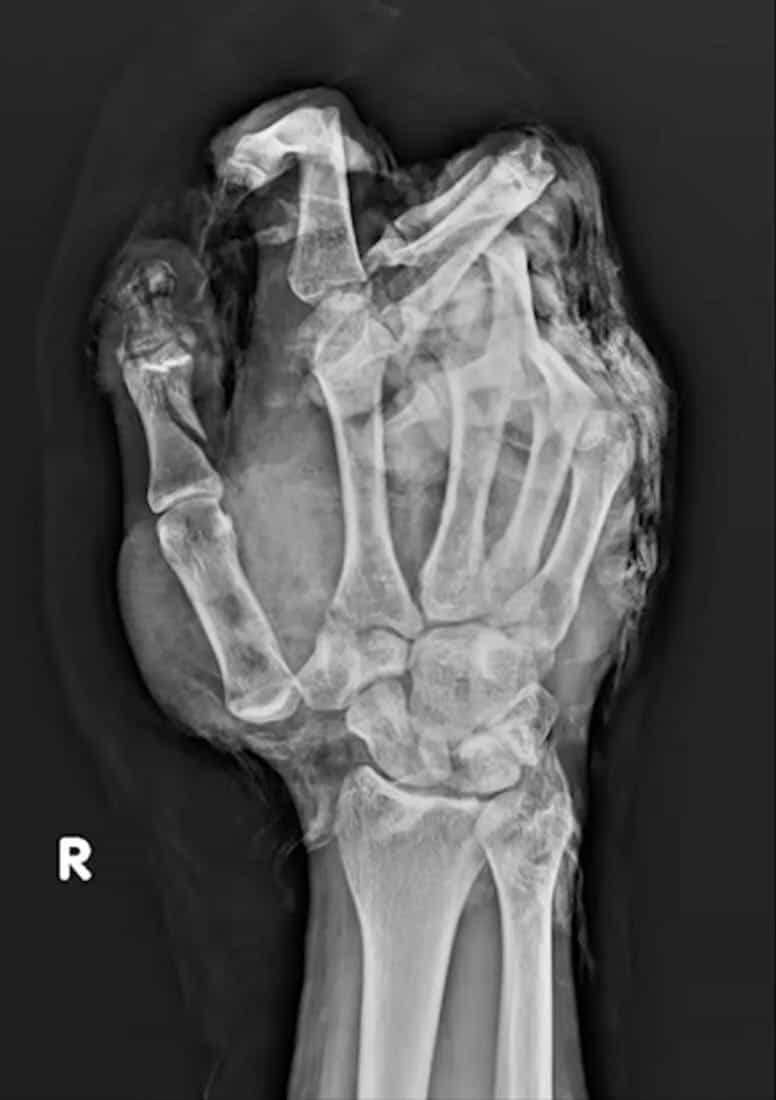

アメリカにて、チャンネル登録者数100万人を超える旅行系YouTuber「Luke Damant」さんが、インドで強力な花火を持っての撮影中、暴発し右手が破壊されてしまう恐ろしい事故動画+その後の衝撃画像など。これにより彼の右手の指は4本になってしまったが、今も元気にYouTube活動を続けているようだ。(※ TOP画はイメージ)